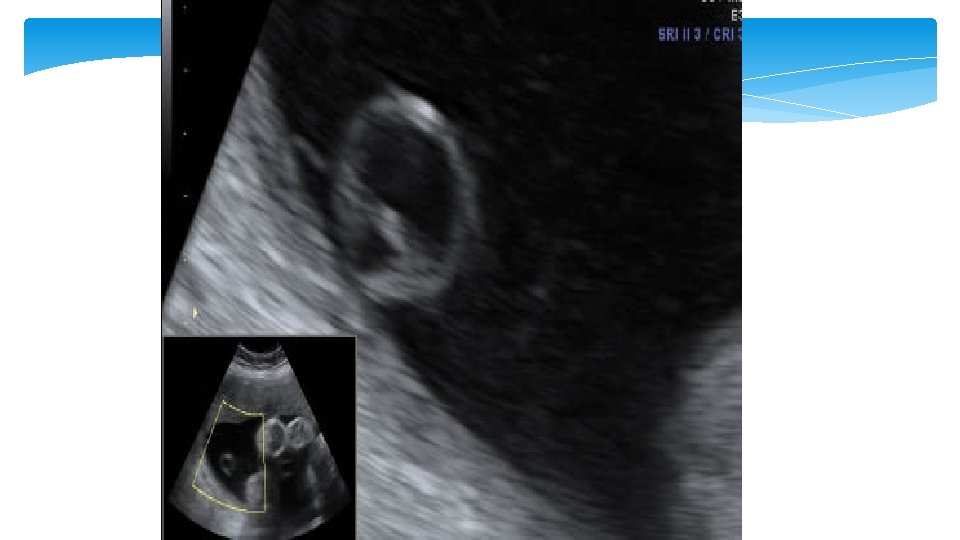

Choriod plexus (CP) cysta Cysts that are seen within the substance of the choroid plexus. They can be single or multiple, unilateral or bilateral, and occur with an incidence of approximately 1%. They may result from entrapement of cerebral spinal fluid with tangled villi. As the stroma of decreases with increasing gestational age this fluid is relased and the cyst resolves. For this reason more than 95% of these cysts resolve by the end of the second trimester